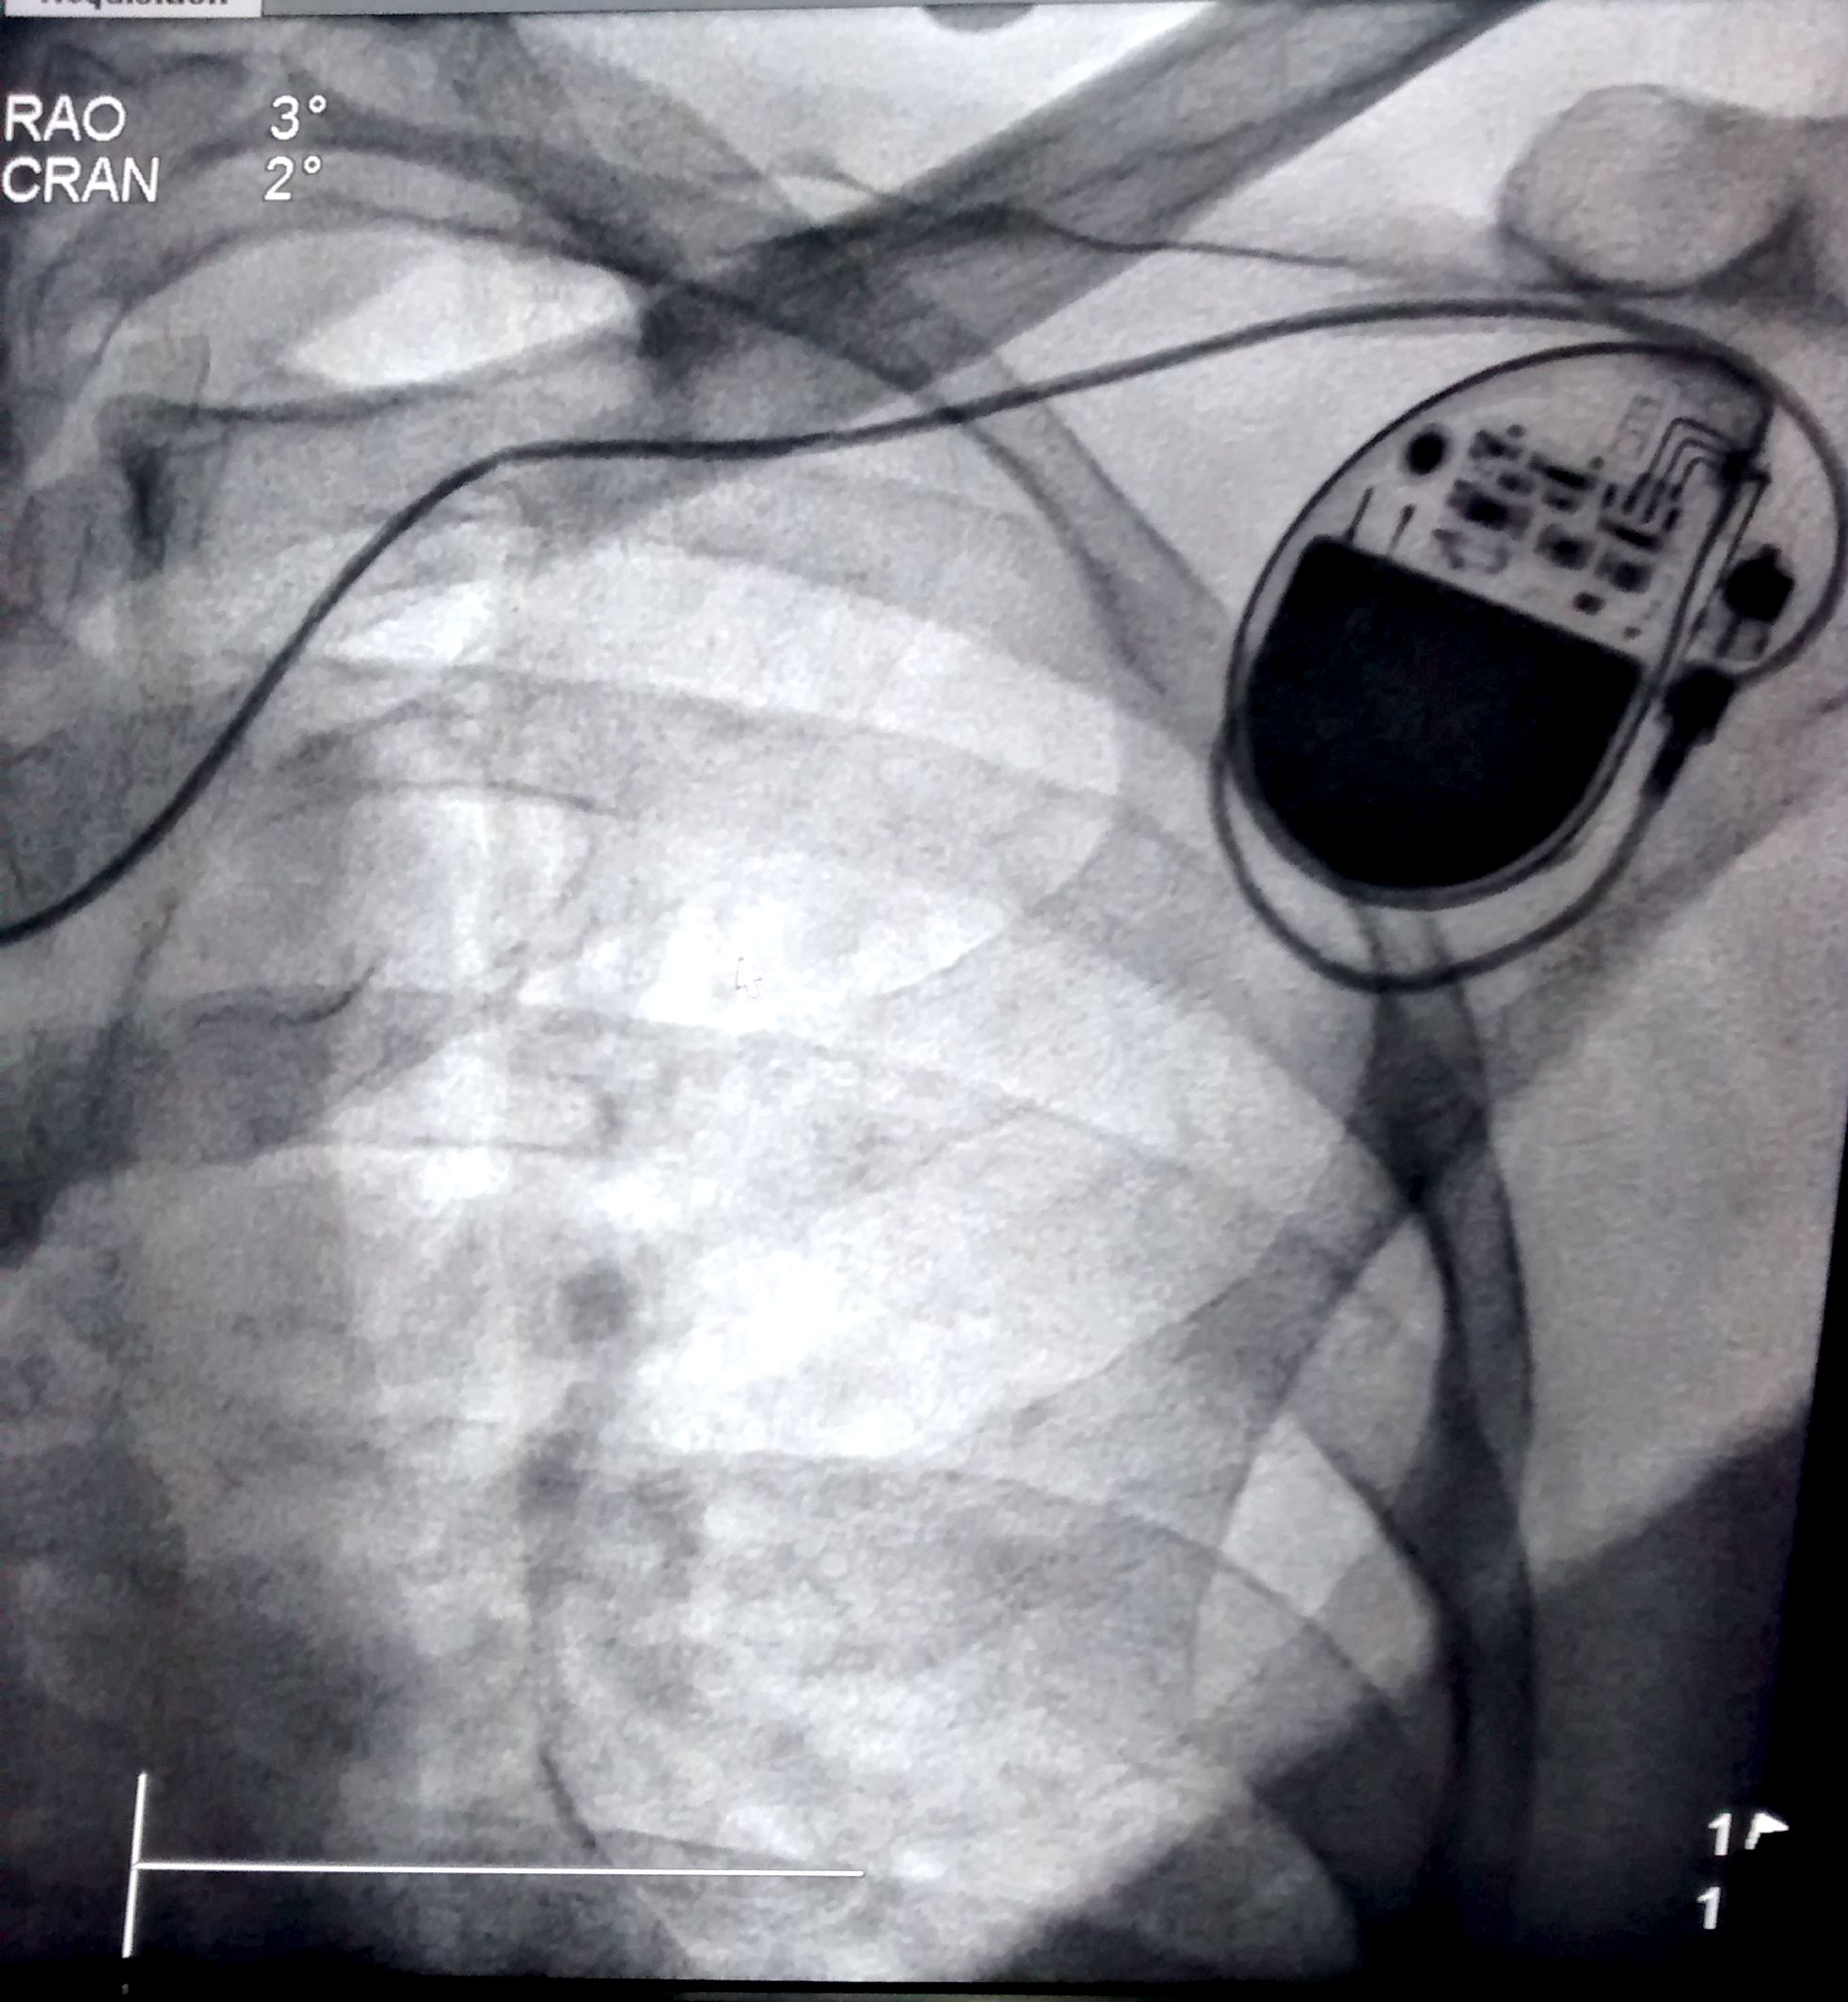

Venogram

• Difficult puncture

• Pre-existing leads

• 10-15 ml of contrast from ipsilateral arm

• Management of stenosis

Puncture with venogram